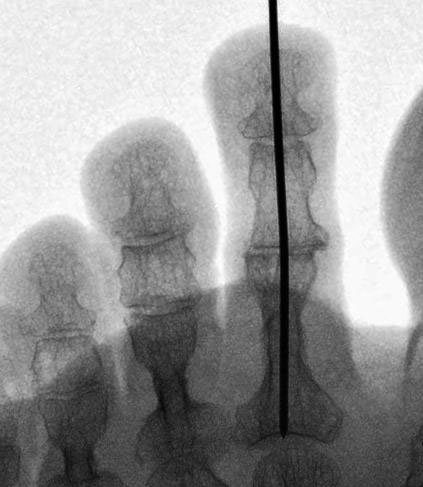

Die vorbereitenden Operationsschritte werden im Abschnitt „PIP-Arthrodese mit K-Draht-Fixierung“ in den Abbildungen 1.1 bis 1.7 beschrieben.

• Eine Röntgenkontrolle wird 6 Wochen postoperativ durchgeführt (Fuß belastet in zwei Ebenen). Besonders geachtet wird auf eine knöcherne Konsolidierung der Arthrodese und auf die Lage eines gegebenenfalls verwendeten intramedullären Implantats.